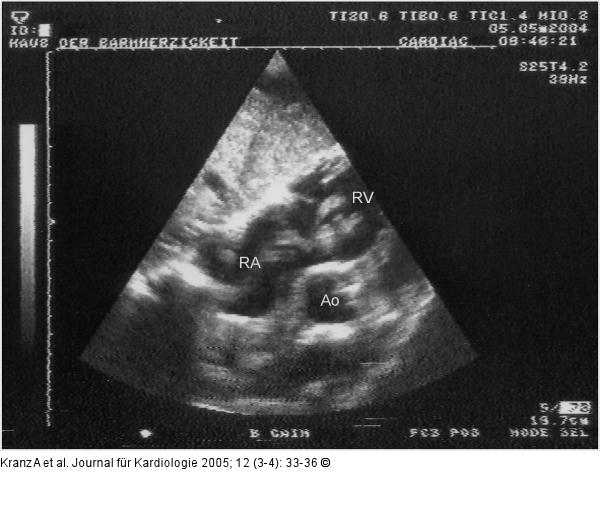

Abbildung 4: Flottierender Thrombus Flottierender Thrombus rechtes Atrium (subkostaler Querschnitt) |

Abbildung 4: Flottierender Thrombus

Flottierender Thrombus rechtes Atrium (subkostaler Querschnitt) |